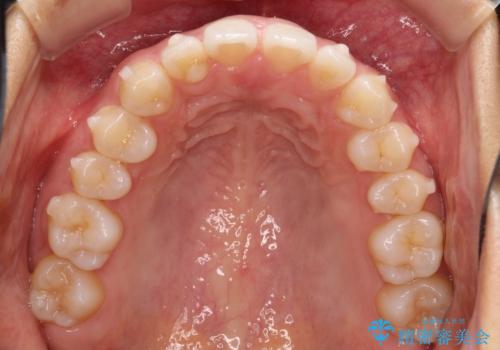

すきっ歯のインビザラインによる目立たない矯正

- すきっ歯を治したいとのことで来院されました。

上下ともに前歯に隙間がありました。

目立たない装置をご希望のためインビザラインで矯正治療を行うこととしました。

使用時間を守っていただけたので、スムーズに治療を終わることができました。